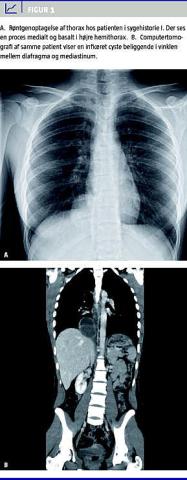

I. En 19 år gammel kvinde blev indlagt på et lokalsygehus pga. smerter i epigastriet, febrilia og dyspnø. Patienten var to år tidligere blevet indlagt med samme symptomer. En eksplorativ laparoskopi, der blev foretaget på mistanke om appendicitis, viste normale forhold. En CT, der blev foretaget ved genindlæggelsen, viste inficeret cyste/absces i mediastinum klos på diafragma ( Figur 1 ). Patienten blev overflyttet til en thoraxkirurgisk afdeling og opereret akut. Ved torakotomi fandt man en stor pusfyldt cyste på 6 cm i diameter indkilet i det nedre lungeligament klos på diafagma og øsofagus. Cysten blev fjernet in toto. Histologisk undersøgelse viste inficeret bronkogen cyste.